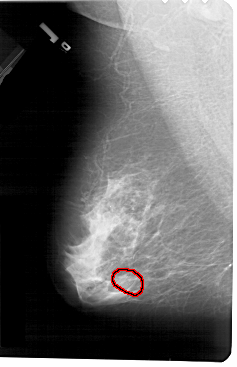

A_1444_1.RIGHT_CC

FILE: A_1444_1.LEFT_CC.OVERLAY

TOTAL_ABNORMALITIES 1

ABNORMALITY 1

LESION_TYPE CALCIFICATION TYPE AMORPHOUS DISTRIBUTION CLUSTERED

ASSESSMENT 4

SUBTLETY 2

PATHOLOGY BENIGN

TOTAL_OUTLINES 1

BOUNDARY